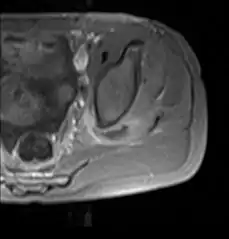

CT exam showing a multiloculated fluid collection in the left gluteus minimus muscle found to be a staph aureus pyomyositis in a 12-year-old healthy boy.

Axial T1 weighted fat suppressed post IV gadolinium contrast enhanced MRI image showing a mutliloculated bacterial abscess in the left gluteal muscle which grew Staphylococcus aureus (methicillin sensitive) thought to be due to tropical pyomyositis.